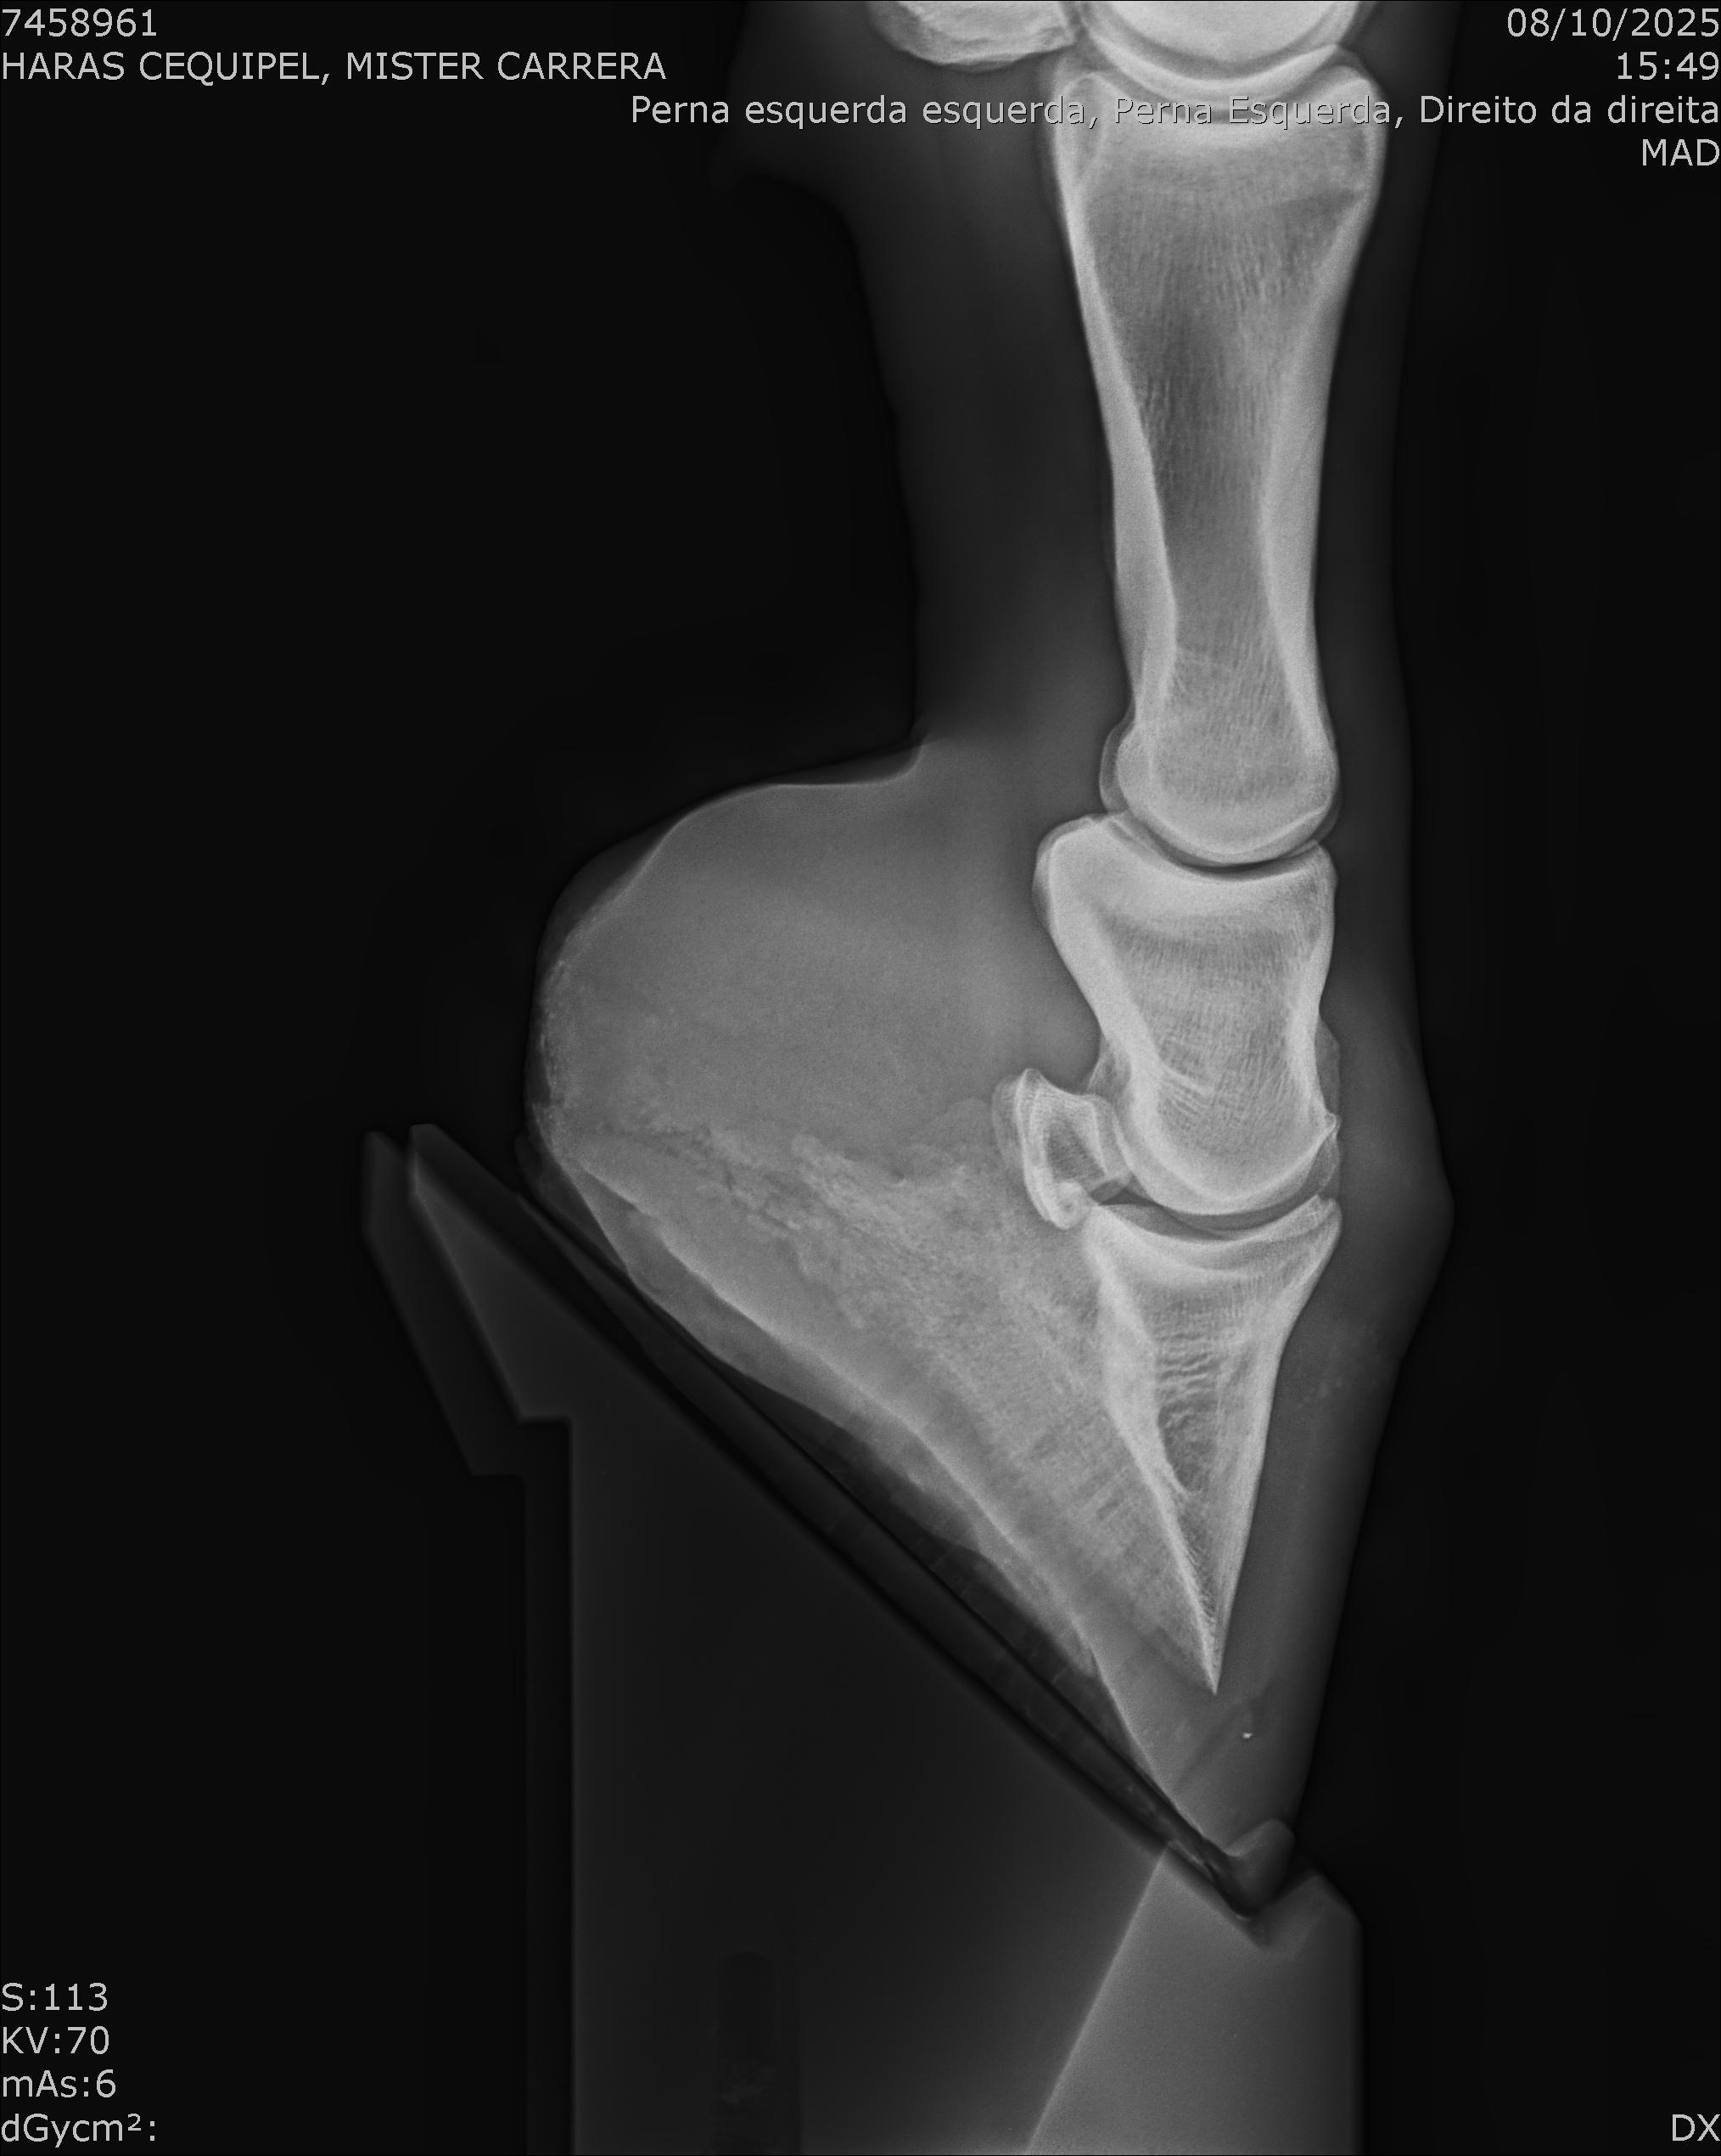

:: RAIOS-X DO LOTE